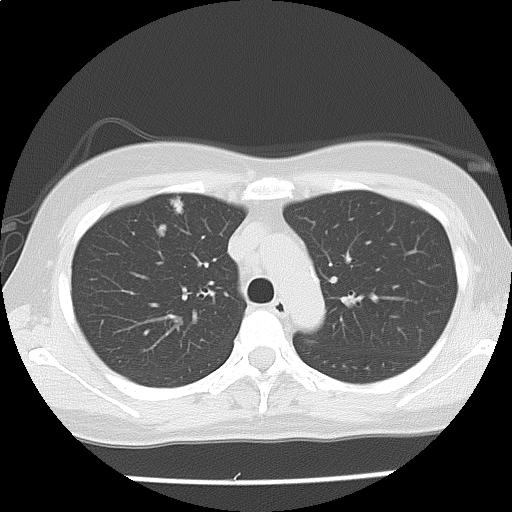

両肺に径数 mm~約9 mm の結節が多発しており(添付画像以外にも認める)、辺縁不整を認める。

多発肺転移の可能性をまず除外する必要があり、原発としては乳癌、膵癌などと考える。

悪性が否定的な場合には、感染症、血管炎、サルコイドーシスなども鑑別に挙げられる。

多発肺結節・縦隔リンパ節腫大:r/o 多発肺転移